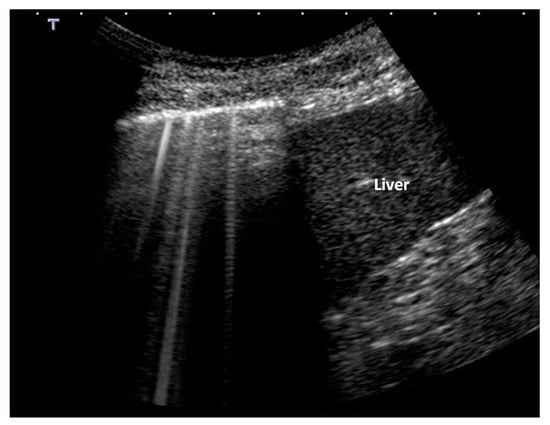

B-Lines are defined as discrete laser-like vertical hyperechoic artifacts that arise with a narrow base from the pleural line, extending to the bottom of the screen without fading, and moving synchronously with lung sliding [1,6]. As B-lines show great heterogeneity and they look different at different levels [7], we will simply call the B-Lines “vertical artifacts” (Figure 2).

Vertical artifacts at the base of the right lung. Early pulmonary edema. Note the presence of a uniform white artifact along with artefact showing clear bands overlap. Early pulmonary edema. (Image obtained with a commercially available machine, Toshiba Aplio XV, equipped with a convex probe, 6 MHz, without harmonic imaging).

From a clinical point of view, they indicate a denser sub-pleural lung, but not yet consolidated, caused by: (1) interstitial pathology enlarging the interstitial tissue but sparing residual peripheral air spaces; (2) pathologic deflations of a normal healthy lung or pathologic subversion of peripheral air spaces; and (3) mixed situations [23,24]. The term “Interstitial Syndrome” can thus be transformed in “Hyperdense pre-consolidated sub-pleural lung”. In cognitive terms, the vertical artifacts in lung sonography represent acoustic information relative to a physical state (porosity or full/empty ratio) of a relatively thin and superficial layer of the lung.